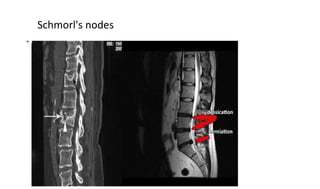

Schmorl's nodes